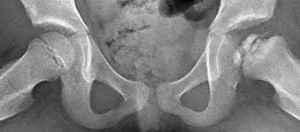

Para comprender su evolución es fundamental analizar las Fases de Waldenström, que describen la historia natural del proceso. La primera es la fase inicial o de necrosis, caracterizada por la isquemia, el cese del crecimiento del núcleo de osificación y una sinovitis que puede durar hasta seis meses. Le sigue la fase de fragmentación, que representa el periodo de mayor riesgo clínico y radiológico; en esta etapa el hueso necrótico es reabsorbido y aparece el signo del creciente, una línea radiolúcida subcondral que indica una fractura inminente y el posible colapso de la cabeza femoral. Posteriormente ocurre la fase de reosificación, donde el tejido óseo nuevo comienza a sustituir al necrótico y finalmente la fase de remodelación, donde la cabeza del fémur adquiere su forma definitiva, la cual dependerá enteramente de la carga mecánica recibida y de la contención articular lograda durante el proceso.

La determinación del pronóstico se basa en tres pilares fundamentales que el clínico debe dominar. El primero y más determinante es la edad al momento del diagnóstico, donde los niños menores de seis años tienen un potencial de remodelación ósea excepcional. El segundo es la Clasificación de Herring o del pilar lateral, que evalúa la integridad de la porción externa de la cabeza femoral durante la fragmentación siendo un pilar mantenido en más del cincuenta por ciento un signo de buen pronóstico. El tercero es la Clasificación de Catterall, que cuantifica la extensión del daño cefálico dividiéndolo en cuatro grados según la cantidad de epífisis afectada.